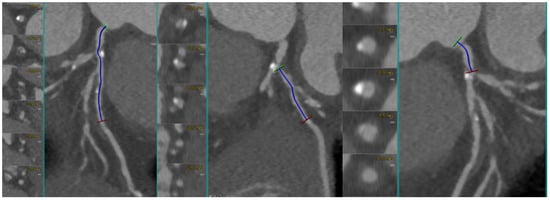

Coronary CT Angiography for PCI Planning and Guidance: A Comprehensive Narrative Review

by Lorenzo Fargione, Pietro Laforgia, Thomas Hovasse, Bernard Chevalier, Nicolas Amabile, Francesca Sanguineti, Stephane Champagne, Thierry Unterseeh, Antoinette Neylon, Neila Sayah, Jerome Garot, Lisa Simioni, Mario Togni, Stephane Cook, Hakim Benamer, Livio D’Angelo, Philippe Garot, Mariama Akodad and Ioannis Skalidis

Coronary computed tomography angiography (CCTA) is increasingly recognized as a comprehensive tool for planning percutaneous coronary intervention (PCI). By integrating plaque morphology, calcium burden, and CT-derived coronary physiology, CCTA enables non-invasive assessment of lesion complexity and supports precision-guided revascularization. This narrative review synthesizes [...] Read more.

Coronary computed tomography angiography (CCTA) is increasingly recognized as a comprehensive tool for planning percutaneous coronary intervention (PCI). By integrating plaque morphology, calcium burden, and CT-derived coronary physiology, CCTA enables non-invasive assessment of lesion complexity and supports precision-guided revascularization. This narrative review synthesizes current evidence on CT-guided PCI from original studies, registries, expert consensus documents, and international guideline recommendations. The literature was identified through PubMed, Embase, and Google Scholar, focusing on CCTA-based plaque characterization, calcium assessment, bifurcation and ostial lesions, chronic total occlusions (CTO), FFR-CT, virtual PCI simulation, and fusion imaging. Particular attention was given to contemporary investigations such as SYNTAX III, P3, and the ongoing P4 trial. CCTA reliably characterizes stenosis severity, plaque distribution, and calcification, demonstrating strong concordance with intravascular imaging. CT-based measurements support accurate stent sizing, prediction of calcium modification requirements, and identification of high-risk features in bifurcation and ostial disease. In CTO PCI, CCTA enhances visualization of proximal cap morphology, occlusion length, tortuosity, and distal vessel quality, outperforming angiographic scoring systems. CT-derived physiology and virtual PCI planning improve lesion selection and allow prediction of post-PCI hemodynamics. Emerging technologies—including photon-counting CT, artificial intelligence-assisted plaque analysis, and CT–fluoroscopy fusion—further expand the applicability of CT-guided PCI. The ongoing P4 trial is expected to provide definitive validation of CT-guided PCI and may support its incorporation into routine clinical workflows. Full article